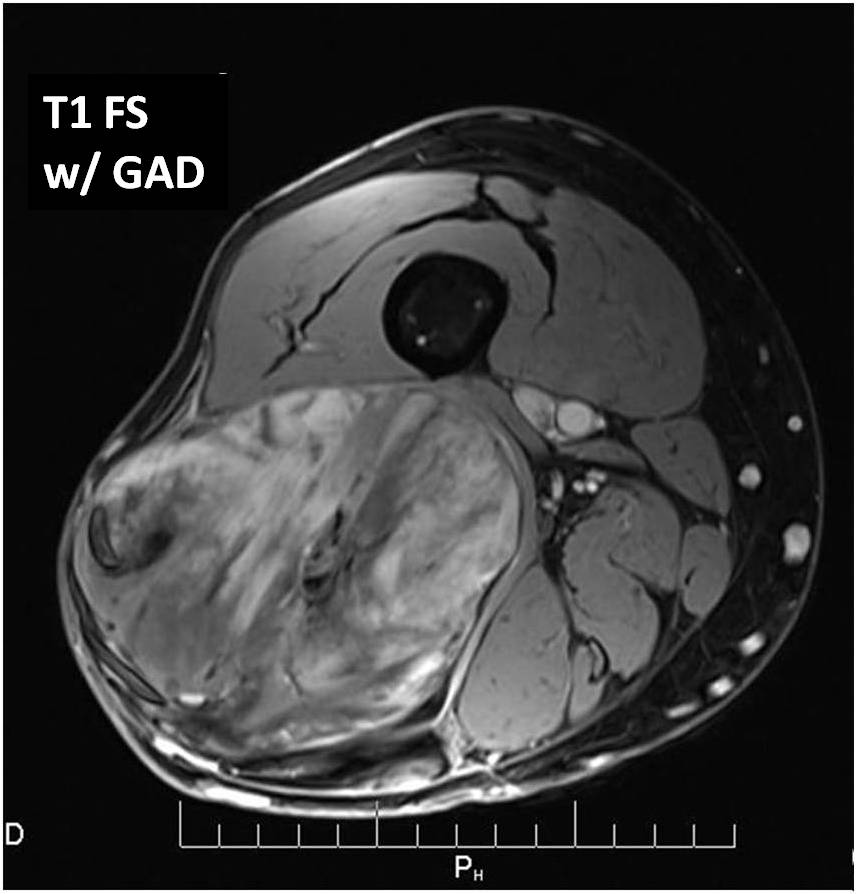

MRI (Fig. 2 and 3)

• Large well defined multilobulated mass.

• Marked high signal on T2 weighted sequence. (may mimic a synovial cyst) (Fig. 2B) The myxoid/mucinous tissue consists of mucopolysaccharides that holds onto water and shows up high signal on T2W images.

• Identification of the subtle fat requires comparison of T1W and T2W images in the same plane but is usually very difficult to discern. (Fig. 2)

Fig 2. T1-weighted MR image (A) of a myxoid liposarcoma demonstrates well-defined mass of intermediate signal intensity with central areas of high intensity. T2 –weighted fat-suppressed image (B) heterogeneously mostly high signal intensity within the lesion.